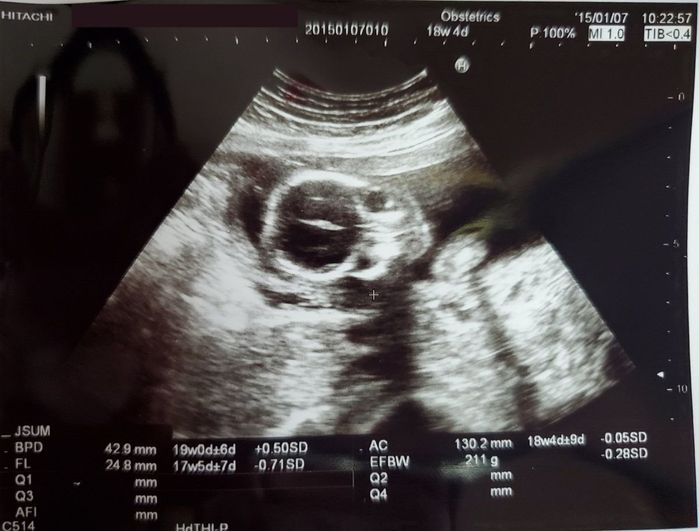

妊娠18週目のエコー写真 - こっちを見つめている!?

赤ちゃんがこちらを向いています。この先のエコーは、なぜか正面を向いているものばかりです。娘は現在4歳ですが、本当に色々なことに興味を持ち、対象となるものをじーっと見つめます。このころからその片鱗を見せていたのかもしれません。私の場合は、妊娠17週に入ったころからつわりも次第に落ち着き、体調が少しずつよくなっていきました。